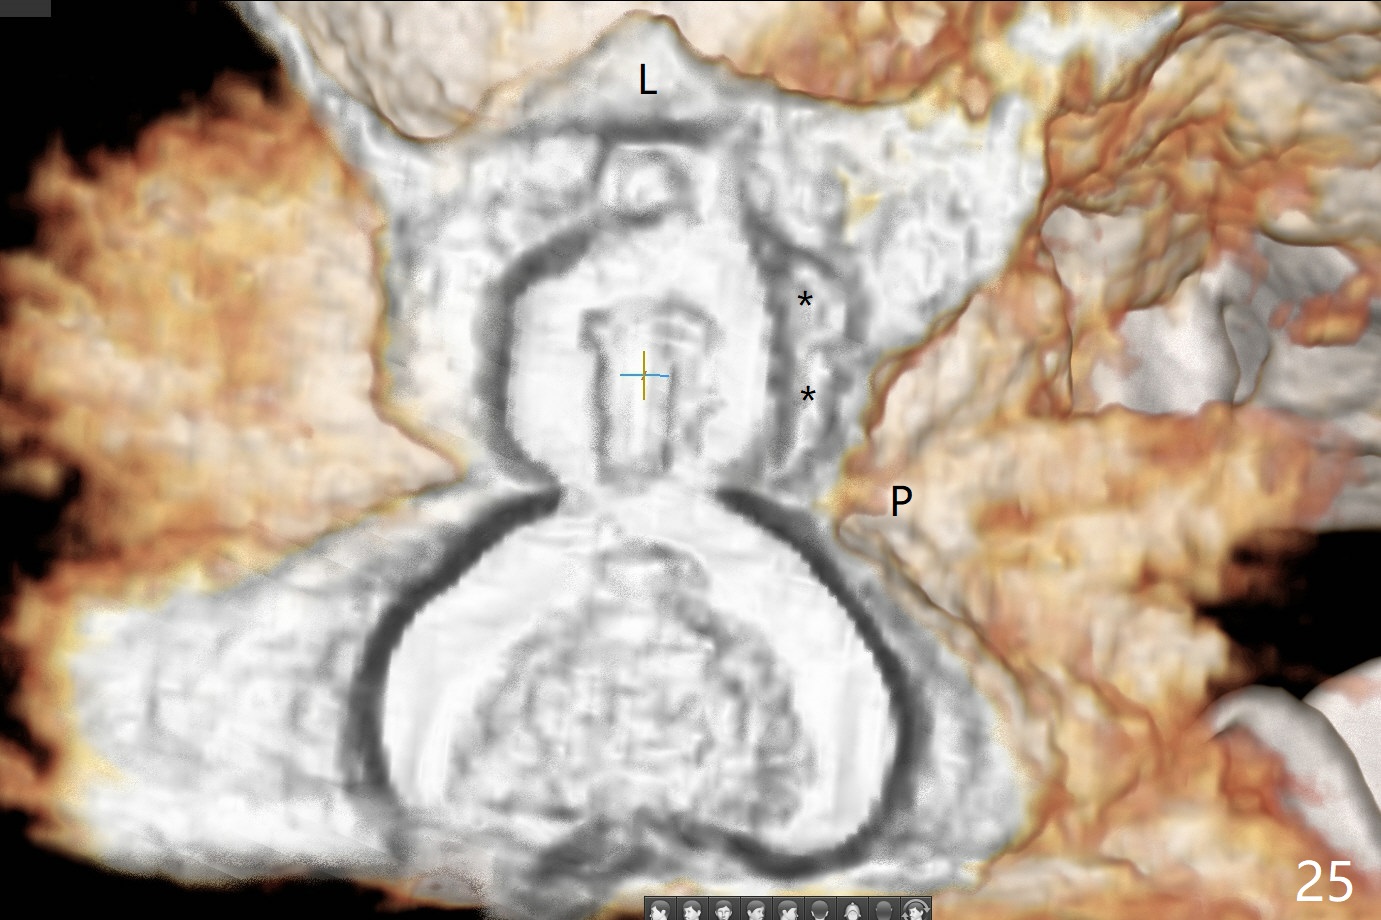

A 45-year-old man has lost the tooth #14 for a while (Fig.1); bone height is 5.4 mm. An extra wide and short implant is planned. Torus palatinus is large, suggesting that bone density should be high. A 6 mm tissue punch is chosen, but it is placed more palatal. If it were placed in the middle of the ridge, there would be no buccal keratinized gingiva (incision may avoid this issue). Additionally, the buccal portion of punch is made incomplete so that there is pedicle on the buccal side when the flap is raised (Fig.4,8: F). It is expected that the excess portion of keratinized tissue will form thick gingiva buccally. Osteotomy proves that bone is dense (Fig.2 (4.5x11 mm tap). Typical sinus lift is finished with placement of 6.4x6 mm (extra wide) bone-level implant (Fig.3, >55 Ncm). Following further torque, Fig.4 shows that the implant (I) is sub-gingival (<). Bitewings are taken to confirm that the implant plateau is at the crestal level (Fig.5,6 ^). PA shows sinus lift (Fig.7 *). The lingual aspect of the implant and healing abutment (H) is further bone grafted and covered by collagen dressing (Fig.8 *). The wound is protected with perio dressing. When the latter dislodges 7 days postop, the collagen dressing and bone graft are lost as well (Fig.10), while the buccal flap remains vital (Fig.9). The lingual exposed plateau should be able to heal normal. The collagen dressing should have been fixed in place by suture or as simple as a dental floss. There is mild nasal hemorrhage 1-2 days postop, possibly related to sinus membrane perforation and inability of Collagen Dressing to cover the perforation and contain the bone graft. When the patient returns for #9 implant placement in 3 weeks postop, the buccal flap reduces in size (Fig.11 *), while the palatal wound has healed with minimal exposure of the implant (Fig.12). Sinus graft remains in place 3 months postop (Fig.13); the buccal flap appears to have incorporated into a part of the gingiva (Fig.14). The bone density of the sinus lift appears to increase 10 days later when an abutment is placed (Fig.15 *). Although oral hygiene is pristine, there is apparent crestal bone resorption 12 months (Fig.16) and 20 months (Fig.17) post cementation, probably due to unfavorable crown/implant ratio and bruxism as well as pre-implantation bone loss (Fig.18,19). In contrast, an immediate implant in the same patient avoids pre- or post-implantation bone loss. In fact both the soft (Fig.20) and hard (Fig.21) tissues remain healthy 2 years 8 months post cementation. The sinus lift remains 3 years 8 months post cementation (Fig.22), while the crestal bone loss persists. The patients keeps complains of food impaction distal associated with bad smell 4 years 1 month post cementation. In fact the distal proximal contact is within normal limit. The bad smell is probably due to crestal bone loss (Fig.23 (pan), 24 (CT) *) and periimplantitis. Bone graft, PRF and Cytoplast membrane will be needed and fixed in place with long healing screw. When the patient returns for crown redo, he also reveals floss related gingival hemorrhage. There is pain associated with palatal sulcus probing with light gingiva erythema. Review of CT coronal section shows possible palatal (Fig.25 P) bone loss (*).